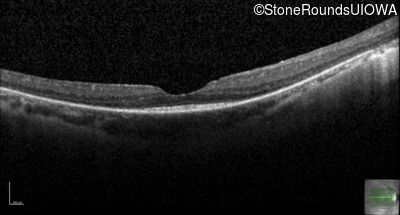

Optical Coherence Tomography - Left - 20/25

Exemplar / OCT Stack